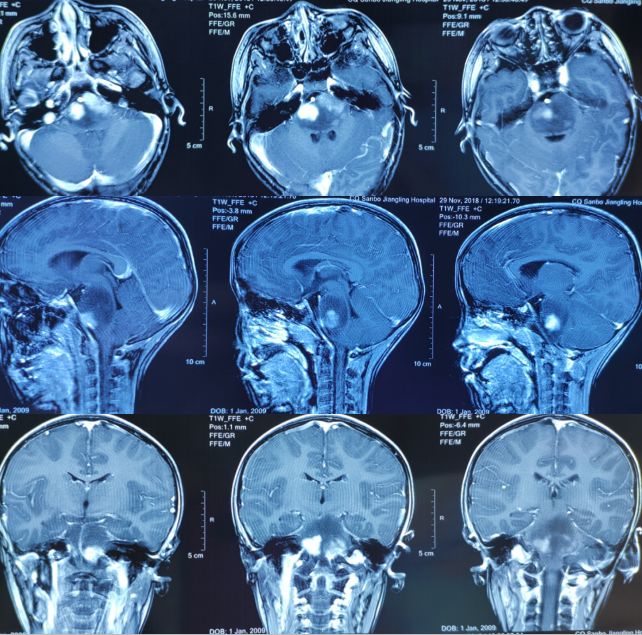

到院后,刘长青主任接诊,仔细询问了孩子的病史,并安排检查,根据检查结果:头颅CT提示脑干低密度占位。MRI提示脑干区占位,最大截面约4.4cm×3.1cm。诊断:脑干占位性病变,考虑胶质瘤可能。

手术前,需做头颅MRIT1、T2、增强T1的无间隔扫描,将数据融合后确定手术靶点。

手术当日,在全麻下为小蕊上头架,前往CT室,行头颅CT轴位的无间隔扫描,经测量、融合,确定坐标值及靶点。

一切准备就绪,刘长青主任采用横窦下、乙状窦后为穿刺进针点,常规切开、钻孔、电凝并打开硬膜。用活检针在同一部位不同方向取出3块病变组织。术中冰冻结果提示:高级别胶质瘤。术后病检结果提示:弥漫性H3K27M突变性中线胶质瘤(WHO Ⅳ级)。